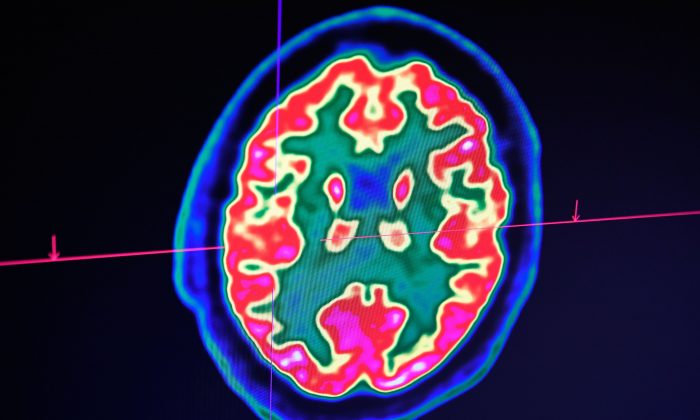

Знімок людського мозку, зроблений за допомогою сканера позитронно-емісійної томографії, також званий ПЕТ-скануванням, видно на екрані Регіонального та університетського госпітального центру Бреста на заході Франції 9 січня 2019 р. (Fred Tanneau/AFP/Getty Images)